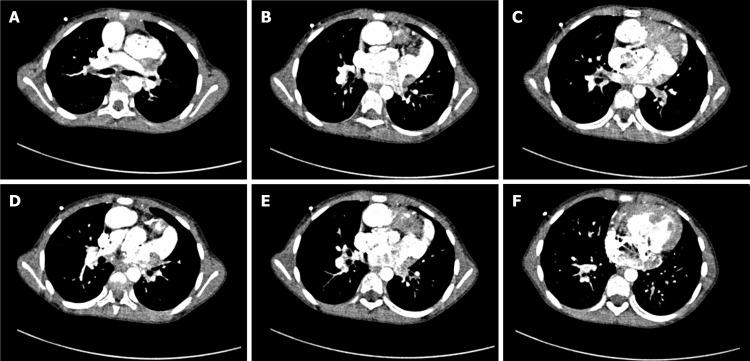

Herein, we report the anesthetic management of a 10-year-old female patient with a DORV. She lived in the low-oxygen Qinghai-Tibet Plateau, and presented with severe polycythemia (hemoglobin, 24.8 g/dL; hematocrit, 75%). She underwent a modified Fontan surgery, which was satisfactory and without any perioperative complications. Our anesthetic management highlights the importance of perioperative hemodilution in decreasing the risk of thromboembolism and the importance of correcting coagulopathy in preventing hemorrhage.

在此,我们报告一名10岁DORV女性患者的麻醉管理情况。她生活在低氧的青藏高原,患有严重红细胞增多症(血红蛋白24.8 g/dL;血细胞比容75%)。她接受了改良Fontan手术,手术效果满意,围手术期无任何并发症。我们的麻醉管理突出了围手术期血液稀释在降低血栓栓塞风险方面的重要性以及纠正凝血障碍在预防出血方面的重要性。